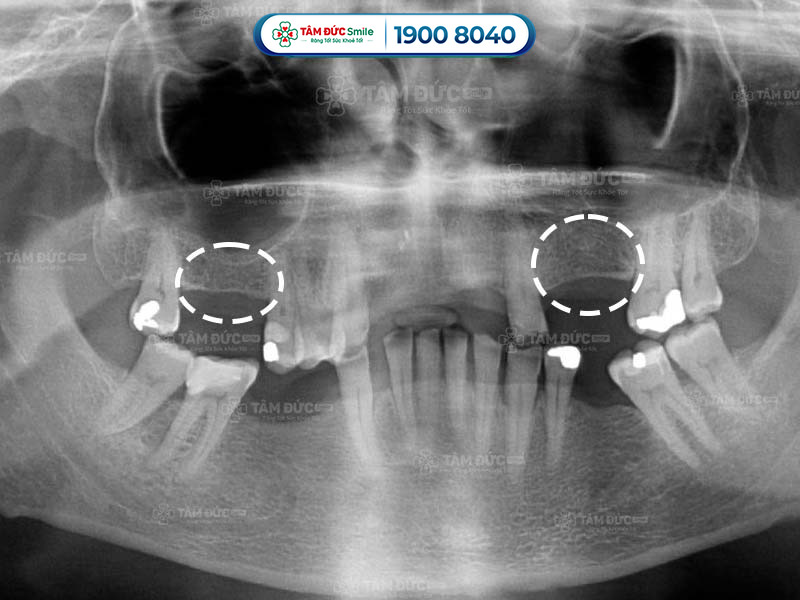

1.1. Quan sát dấu hiệu tiêu xương răng qua phim chụp X-Quang

Một trong những dấu hiệu tiêu xương răng rõ ràng nhất là hiện tượng hạ thấp của sàn xoang hàm. Sàn xoang hàm là một vách ngăn mỏng nằm giữa xoang hàm và xương ổ răng. Khi răng bị mất, lực nhai không còn tác động lên vùng xương ổ răng, làm cho xương ổ răng teo dần.

Trên phim chụp X-Quang, bác sĩ dễ dàng nhận thấy sự hạ thấp của sàn xoang hàm. Sự hạ thấp này được đánh giá bằng cách đo khoảng cách từ sàn xoang đến nướu răng.

dấu hiệu tiêu xương răng qua từng giai đoạn

Dấu hiệu tiêu xương răng qua phim X-Quang